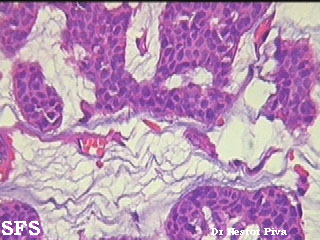

There are solid and cystic aggregations of neoplastic cells within the dermis, often with extension to the subcutis, embedded in large pools of mucin. Mucinous areas are typically separated by fibrous septae.